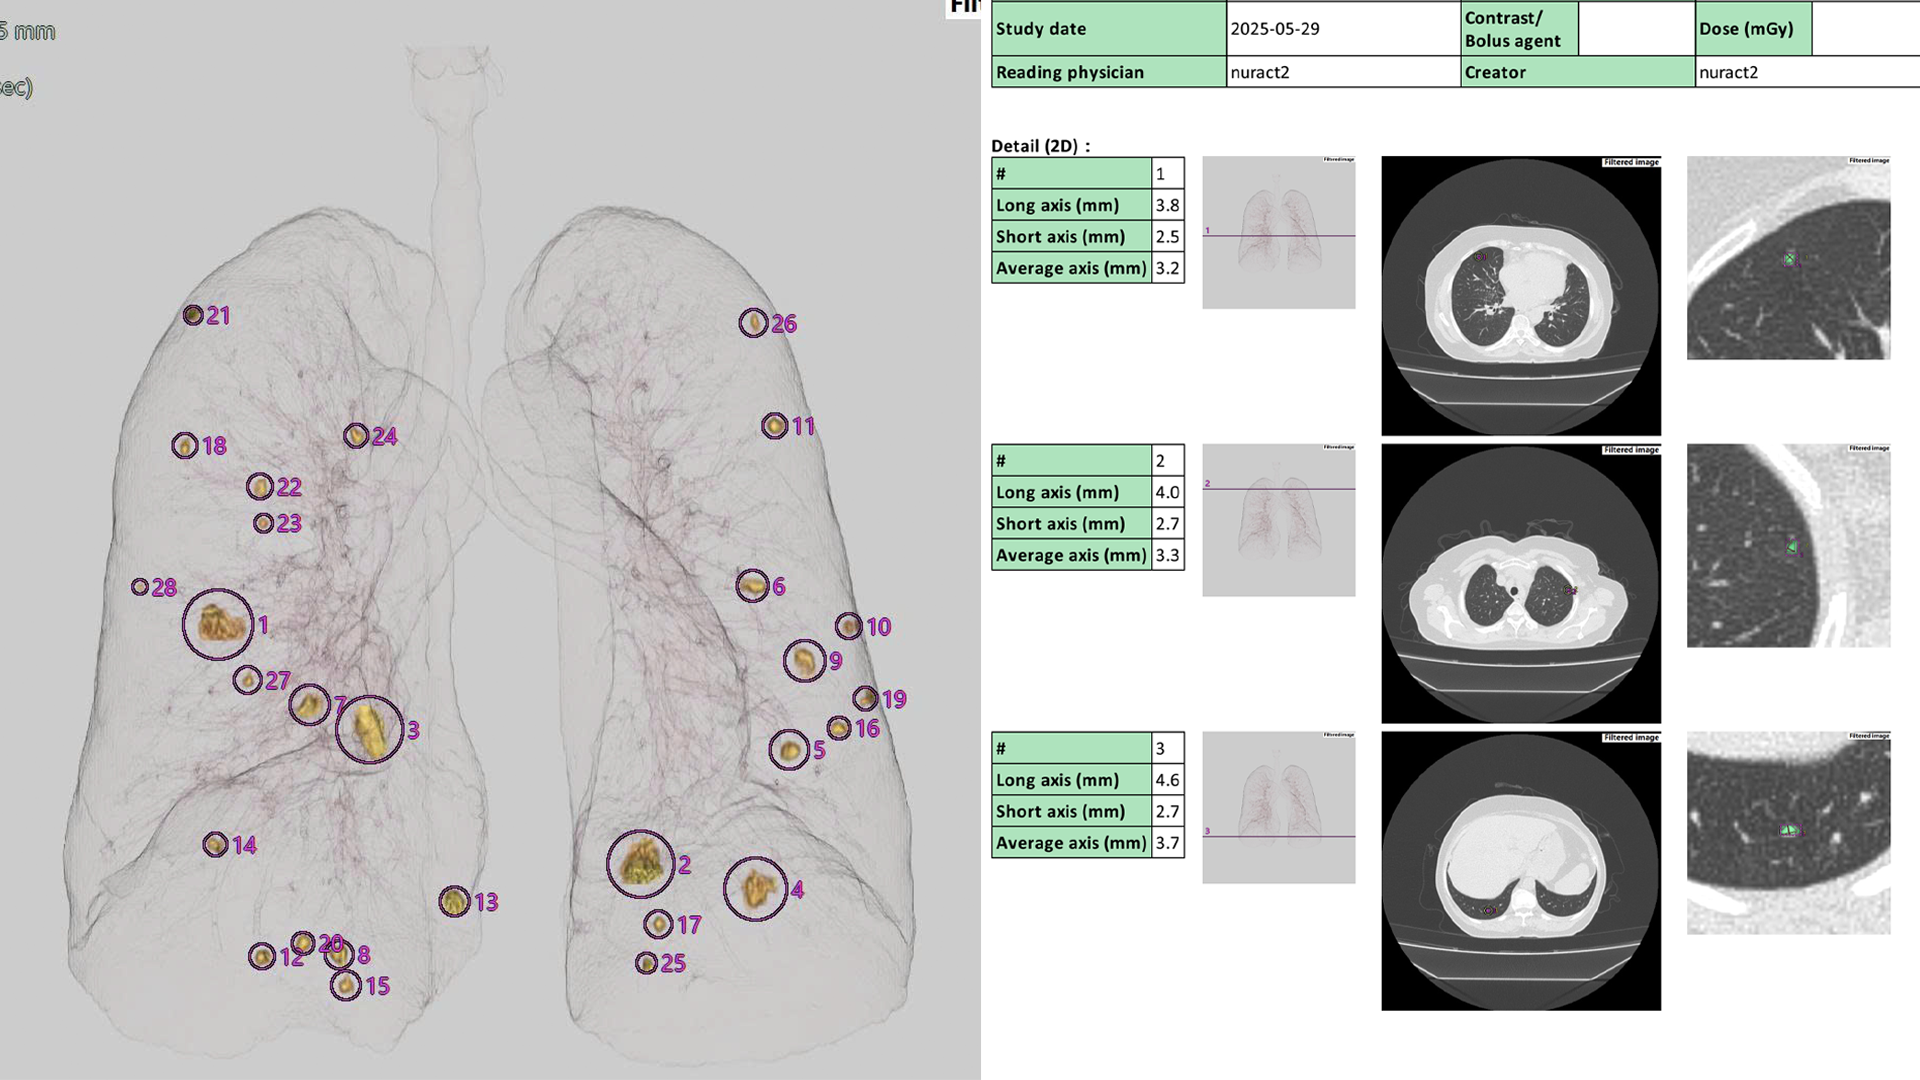

A chest CT scan using AI technology for a 62-year-old female patient on 29/5 revealed 24 small lesions ranging from 2 mm to 9 mm, diagnosing ovarian cancer metastasized to both lungs. Photo: Nura